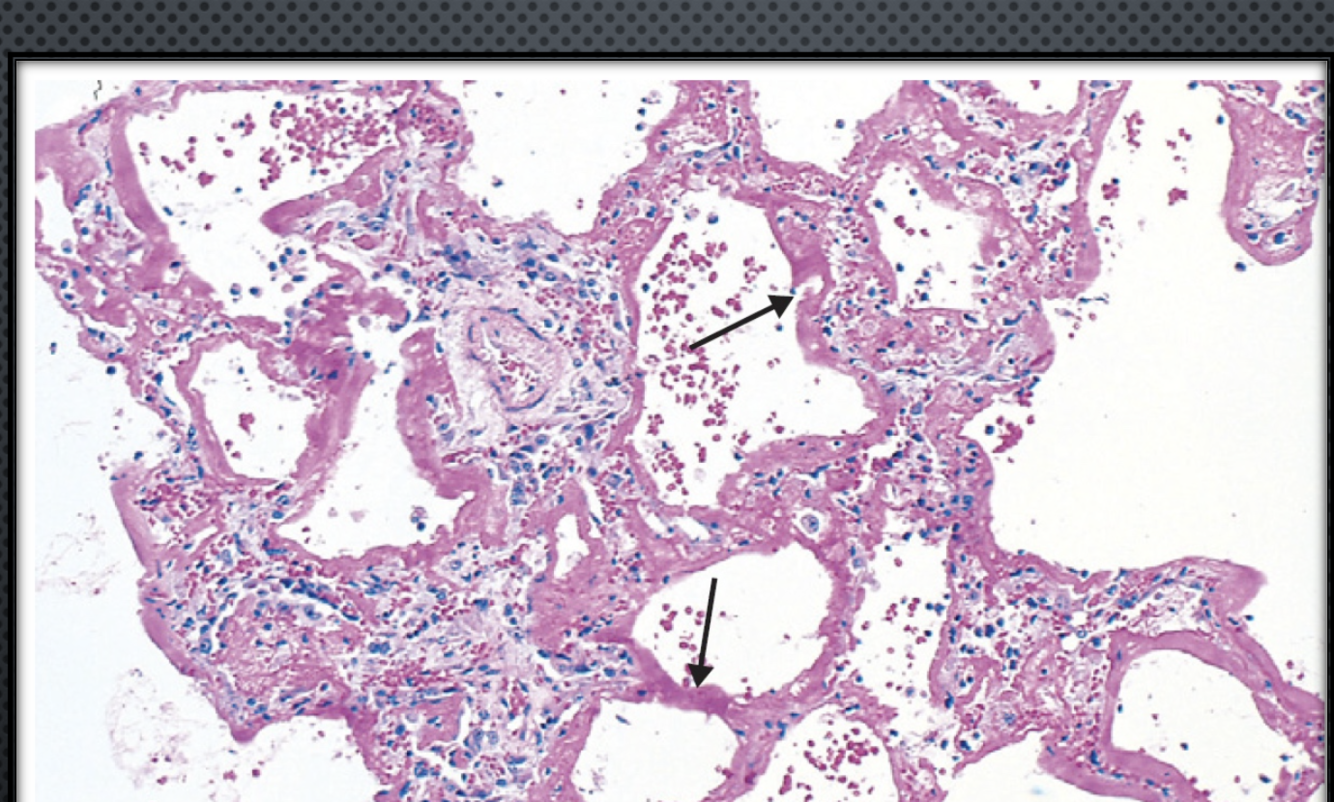

Xray shows bilateral hilar enlargement, and biopsy shows this:

Sarcoidosis presents with non-necrotizing granulomas